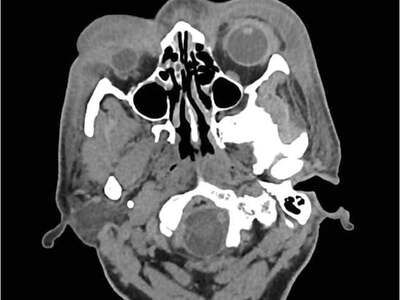

This was a 62-year-old man with type 2 diabetes who was assaulted with a wooden plank and rusty nail on his frontal scalp area sustaining a laceration 3 days prior. The laceration was sutured and a head injury was ruled out with a CT scan.